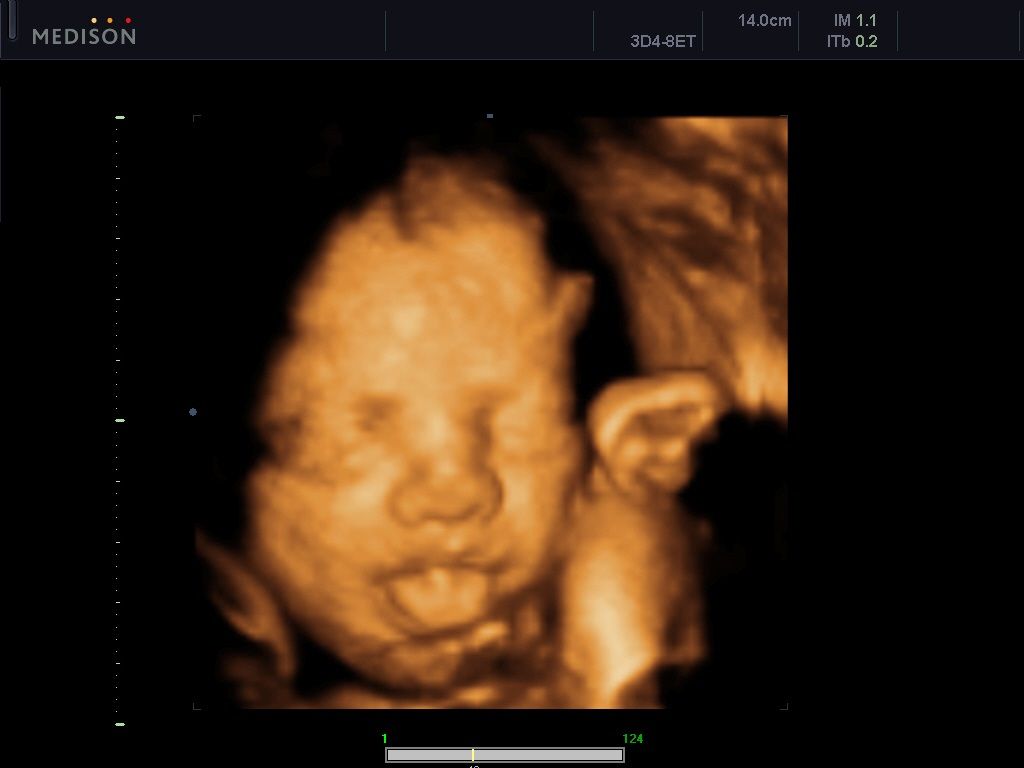

La ecografía 3D es una prueba de imagen no invasiva que permite ver la imagen del feto en el útero materno en diferentes planos y en diferentes ángulos. Tal imagen muestra a los futuros padres mucho mejor que el ultrasonido bidimensional. En la versión de ultrasonido 4D, además, puedes observar al bebé en tiempo real, observar sus movimientos y expresiones faciales. La prueba más valiosa se realizará en el tercer trimestre del embarazo.

Luego, el médico cambia los parámetros técnicos del aparato y evalúa al feto utilizando la técnica 4D. En la ecografía 4D puedes girar el feto casi libremente en la pantalla de la cámara, obteniendo cortes transversales no disponibles en la exploración tradicional, lo que supone una gran ventaja, ya que la imagen obtenida en dos dimensiones depende muchas veces de la posición del feto en el momento de la ecografía.

- Imagen realista de la cara y el cuerpo del niño gracias a la Ecografía 4D.

- La capacidad de observar movimientos, expresiones faciales, sonreír

El valor emocional del examen de ultrasonido 4D no puede pasarse por alto. Puedes ver a tu bebé, sus movimientos, la cara y en las últimas semanas antes del nacimiento, incluso los gestos y las expresiones faciales. Esto le permite construir un vínculo emocional con el bebé incluso antes de tomarlo en sus brazos por primera vez y aliviar el estrés o el miedo a dar a luz.